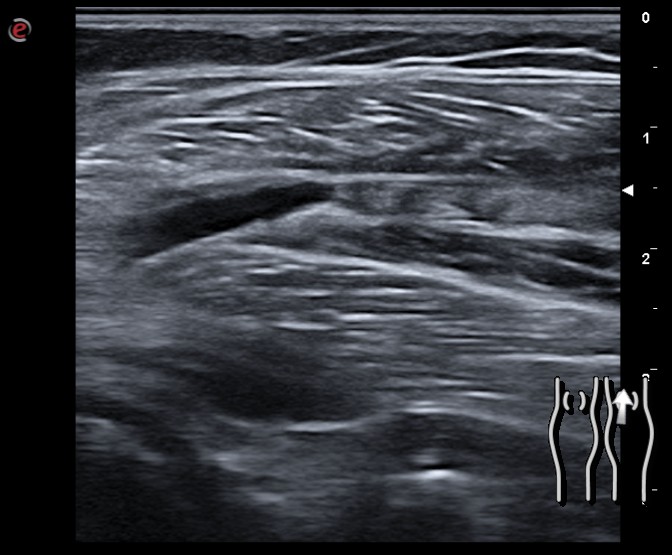

Durante el seguimiento se produce un empeoramiento del dolor en la región inferior al hueco poplíteo y en la ecografía se constata una progresión de la trombosis venosa. Se decide inicio de anticoagulación, en primer lugar con enoxaparina y después con dabigatrán durante 3 meses. Tras 2 meses de evolución presenta una evolución satisfactoria y a los 3 meses no hay datos de trombosis en la ecografía.